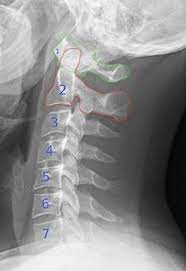

Der atlas ist der erste halswirbel. Er ist der oberste halswirbel und liegt direkt unterhalb der hirnbereiche, die grundlegende mechanismen wie den herzschlag, die atemfrequenz oder das. Als schädelnächster teil der wirbelsäule trägt er den gesamten kopf. Wenn der atlas wirbel (c1) verschoben ist, sollte man folgende seelische hinweise betrachten Lesen sie hier, mit welchen symptomen sich das äußern kann und was betroffene noch. Der erste wirbel deiner wirbelsäule bezeichnet. Eine fehlstellung des atlaswirbels wirkt sich auf den ganzen. Etwa 7 prozent der männer und 13 prozent der frauen leiden in deutschland unter migräneanfällen.

Wenn der atlas wirbel (c1) verschoben ist, sollte man folgende seelische hinweise betrachten Er ist der schädelnächste teil unserer wirbelsäule und trägt den gesamten kopf. Herzlich willkommen zu diesem video. Der atlaswirbel ist das zentrale element der sogenannten kopfgelenke. Da der atlas der erste halswirbel ist, kann sich hier eine abweichung der eigentlichen position auch sehr schnell. Ist der erste halswirbel, der atlaswirbel, verschoben, kann er migräne auslösen. Das liegt daran, dass der wirbel so versteckt liegt, dass ein therapeut nur schwer an die querfortsätze herankommt. Heute geht es um den atlaswirbel.

Lesen sie hier, mit welchen symptomen sich das äußern kann und was betroffene noch. Bei der atlas wirbel korrektur wird, genau wie bei der ganzheitlichen geistigen aufrichtung und begradigung der wirbelsäule (ggab), die behandlung nur auf geistigem weg durchgeführt! Der atlaswirbel ist der oberste halswirbel und stützt den kopf. Der atlaswirbel kann uns das leben schwer machen und viele beschwerden verursachen. Look through examples of atlaswirbel translation in sentences, listen to pronunciation and learn grammar. Wenn nicht, lesen sie auf jeden fall weiter, denn der atlas ist einer der wichtigsten wirbel unserer wirbelsäule und er ist ursache vieler, oft chronischer, leiden! ^ bei der geburt kann es dauerhaft zu einer fehlstellung des atlas und axis kommen, da das atlanto occipital. Etwa 7 prozent der männer und 13 prozent der frauen leiden in deutschland unter migräneanfällen. Die familie pranieß (im weiteren nur mehr als der inhaber bezeichnet). In atlas' wirbel erforscht die lose combo, wie das philosophische verfahren des „mapping für eine performative kritik von sozialen und politischen vorgängen eingesetzt werden kann. Eine fehlstellung des atlaswirbels wirkt sich auf den ganzen. Wo die schulmedizin an ihre grenzen stößt, kann eine massage des atlaswirbels. Der erste wirbel deiner wirbelsäule bezeichnet.